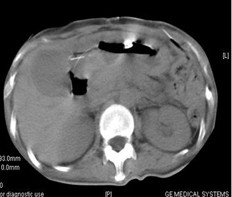

男,60歲,晚期胃癌,腹腔轉(zhuǎn)移,鎖骨上淋巴結(jié)轉(zhuǎn)移,肝,腹腔轉(zhuǎn)移。初治(手術(shù))。治療前CEA 12.95 ng/ml,左鎖骨上轉(zhuǎn)移淋巴結(jié)2.0cm。今又生經(jīng)靜脈滴注,1×1012VP/支/次,3次/周,共30支,聯(lián)合草酸鉑+CF+5-FU化療,2周期。治療后:CEA下降到9.71 ng/ml,左鎖骨上轉(zhuǎn)移淋巴結(jié)縮小到0.5 cm。KPS評(píng)分增加20分,療效評(píng)價(jià)為腫瘤部分消退(PR)。

治療前

治療后